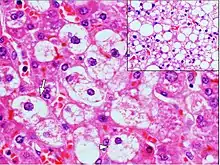

Micrograph demonstrating marked (macrovesicular) steatosis in non-alcoholic fatty liver disease. Masson's trichrome stain.

Histopathology of microvesicular steatosis, with foamy hepatocytes (two annotated by arrows), as opposed to macrovesicular steatosis (insert).

Microvesicular steatosis is characterized by small intracytoplasmic fat vacuoles (liposomes) which accumulate within hepatocytes.[9] It is associated with a wide variety of conditions, including alcoholism, drug toxicity of several medications, delta hepatitis (in South America and Central Africa), sudden childhood death, congenital defects of fatty acid beta oxidation, cholesterol ester storage disease, Wolman disease and Alpers syndrome.[10]

Steatosis reflects an impairment of the normal processes of synthesis and elimination of triglyceride fat. Excess lipid accumulates in vesicles that displace the cytoplasm. When the vesicles are large enough to distort the nucleus, the condition is known as macrovesicular steatosis; otherwise, the condition is known as microvesicular steatosis. While not particularly detrimental to the cell in mild cases, large accumulations can disrupt cell constituents, and in severe cases the cell may even burst.